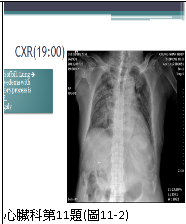

11. 病人82歲男性,主訴有寒顫(chills)及漸進性呼吸困難的兩天病程,同時伴有咖啡色嘔吐物。他有高血壓、左迴旋枝支架置放之冠心病及腦中風而左半邊麻痺的多年病史。血壓 125/64;心跳 100/min;體溫 38.6度;呼吸 24/min;心尖部有Gr 4/6 systolic murmur;肺部有濕性濁音,雙腳水腫;其他尚無重大異常。實驗室:WBC 9610/mm3,segment neutrophils 88%;Hb 10.0 g/dL;C-Reactive protein 1.69 ng/mL;CK 221 ng/mL; CK-MB 16 U/L;Troponin I 1.36 μg/L;尿檢有蛋自尿(++),大便潛血,(++);其心電圖及胸部X光如圖11-1及圖11-2所示。三、八及十二小時後之CK及CK-MB,分別為1340、1462、1422及40、44、38。且在翌日追蹤胸部X光如圖11-3所示。隨即 (1).逕行血液及痰細菌培養及啟用Unasyn 1g q8h及azithromycin 500 mg qd (2)輸2u packed cell RBC (3).靜脈注射Furosemide 20 mg (4)使用Clopidogrel 150 mg & then 75 mg qd 及Aspirin 80 mg qd (5)Heparin25,000 u/day (6)會診心臟科 請問下列哪一組的處置較恰當? (A) (1)+(2)+(5) (B) (1)+(3)+(6) (C) (1)+(4)+(6) (D) (2)+(5)+(6) (E) (3+(4)+(5)